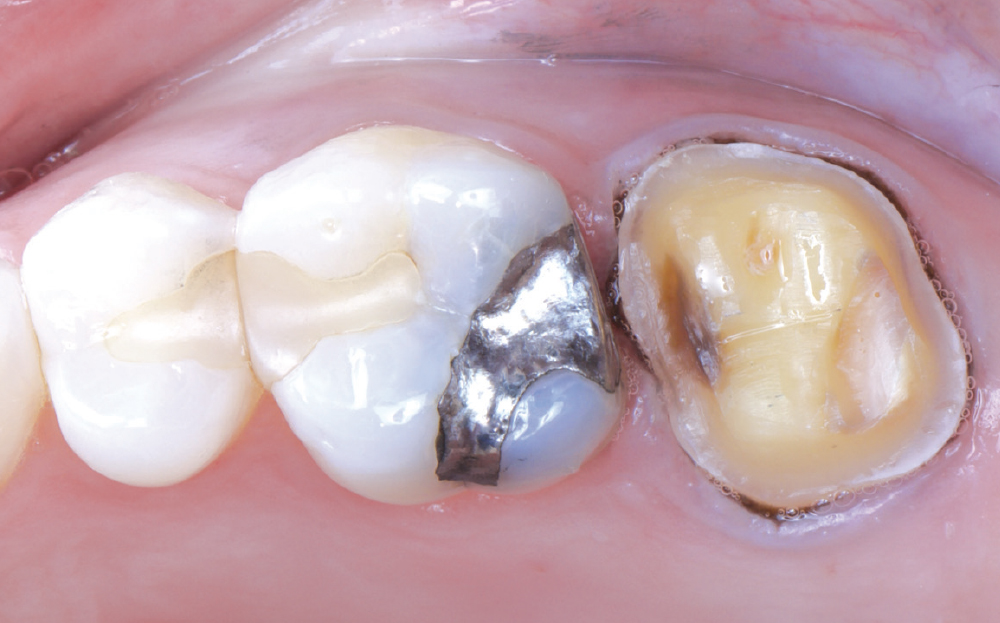

Even though she is a dental hygienist, Nikole decided to wait it out when she was told her crown on tooth #15 had an open margin. But over time, she noticed the area started to shred her floss. That’s when she decided it was time for the crown to be replaced.

Because the patient had high expectations for her restoration, I selected a BruxZir® Esthetic NOW Posterior Milling Block for its combination of esthetics and strength. Though BruxZir Esthetic was originally developed with the anterior in mind, with a yttria content that enhances the overall translucency and color, the material still maintains an excellent flexural strength of 870 MPa, meaning it is sufficiently strong enough to be used anywhere in the arch.